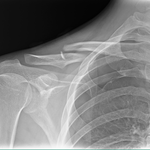

●右鎖骨骨折

当患者さんは手術療法に強く抵抗があり当院での保存療法を選択されました。

骨折部位の短縮転移があたので整復操作が必須になります。運よく短縮転移が矯正されたので保存療法で経過をみました。暑い時期だったので来院の度に固定を外し体を清拭して施術後、新しい下着の上から再度固定をする運びになりました。

骨折部位には超音波、患部以外の所は関節運動、経過を見て軽いマッサージを開始。固定も少しずつ簡易な物へ変更し二カ月後には三角巾のみ、三ヵ月経過すると肩関節の挙上もできるようになりました。

経過良好で完治しました。

左のレントゲンは短縮転位 (受傷時) 右は整復操作をして骨片が重なり合っている状態